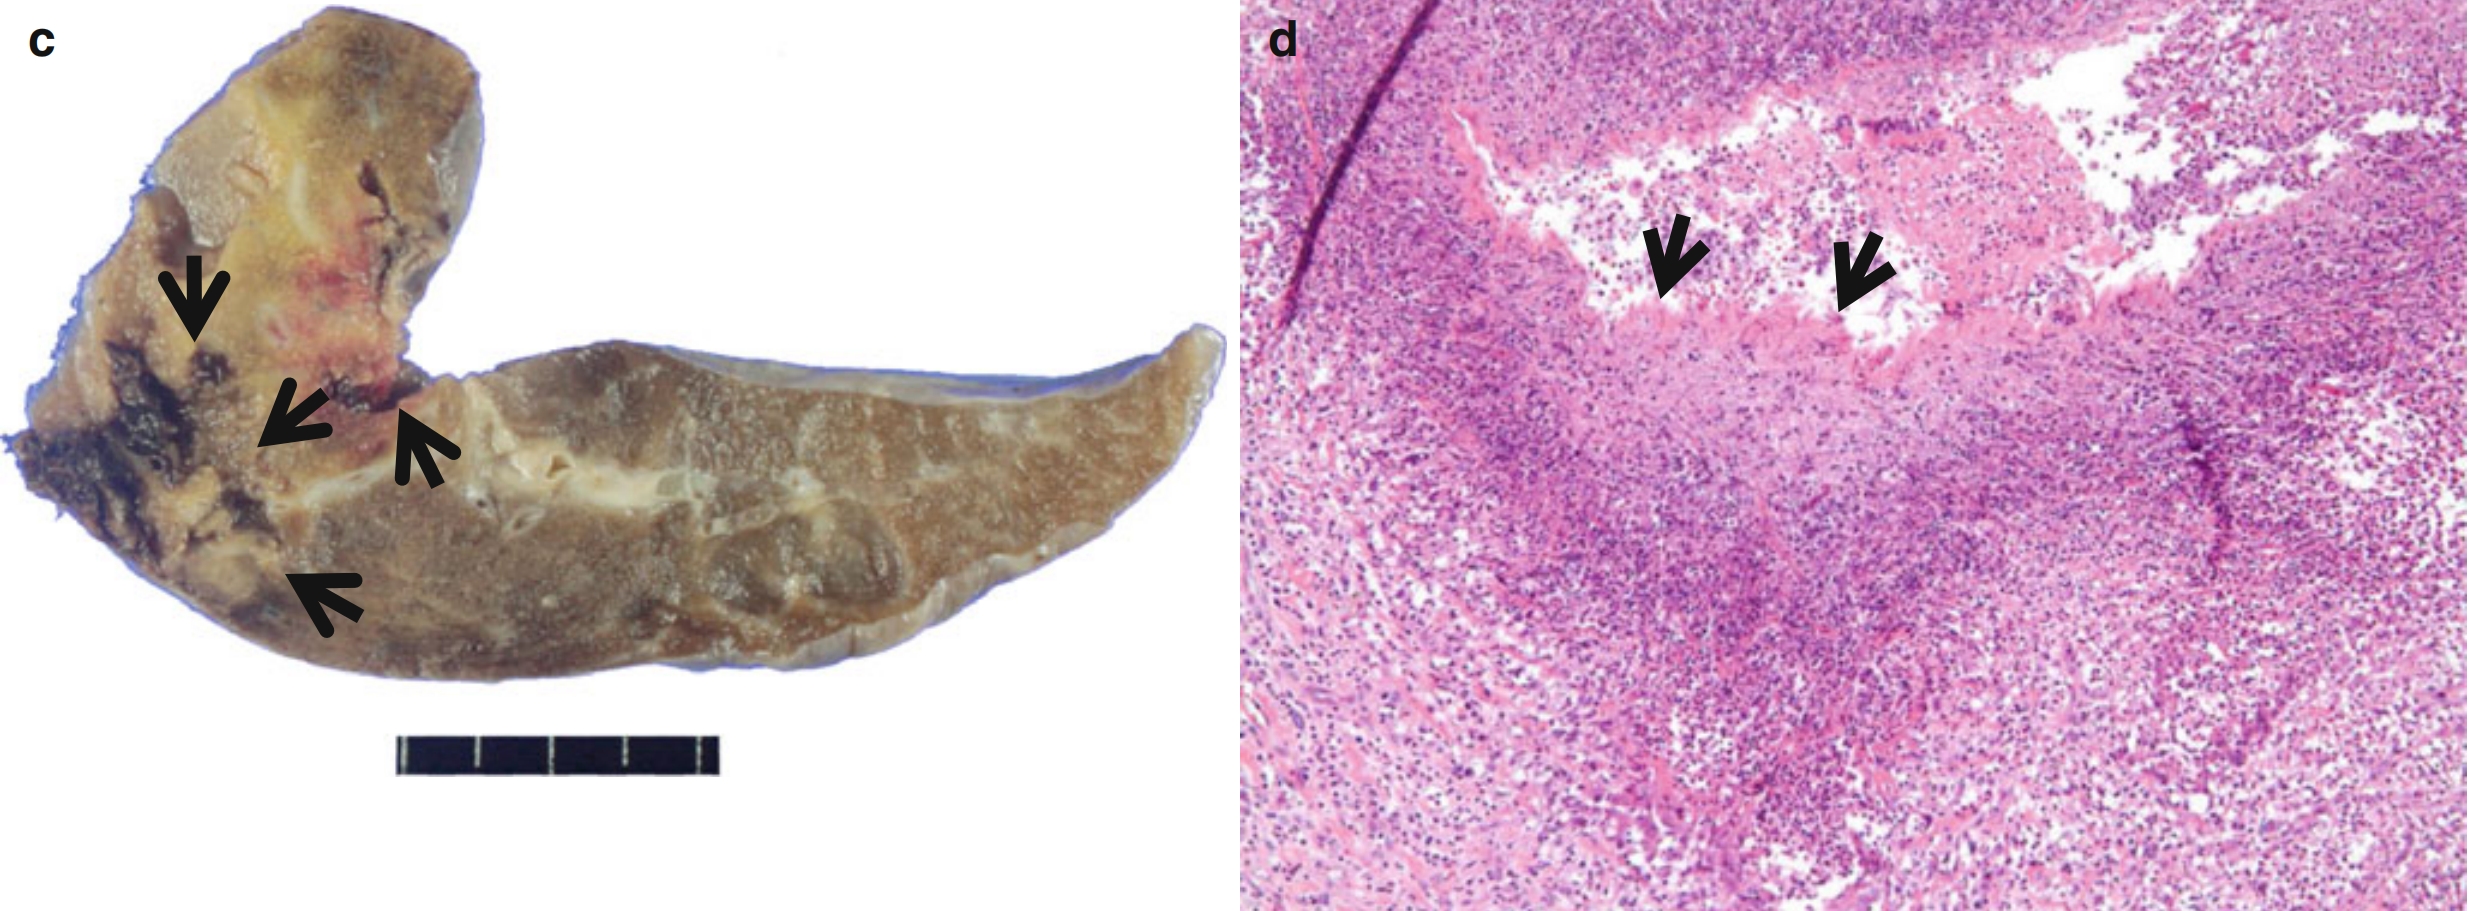

图8.4 男,70岁,淋巴瘤样肉芽肿病患者、可见反晕征。

CT扫描(层厚=5.0mm)肺窗于左肺下叶支气管水平可见双肺多发大小不等的结节,双侧肺门淋巴结肿大。部分结节可见反晕征(箭头所示)。

CT-病理对照:在组织学上,肺内结节和肿块为血管内和血管周围不典型淋巴样细胞浸润导致。病灶中央低密度区为中央坏死区,而结节外围环状强化,则与淋巴瘤样肉芽肿病的血管受侵、破坏有关。

淋巴瘤样肉芽肿病的反晕征,可能与气腔中心被水肿液和泡沫样组织细胞充填及更密集的周围淋巴细胞浸润有关。